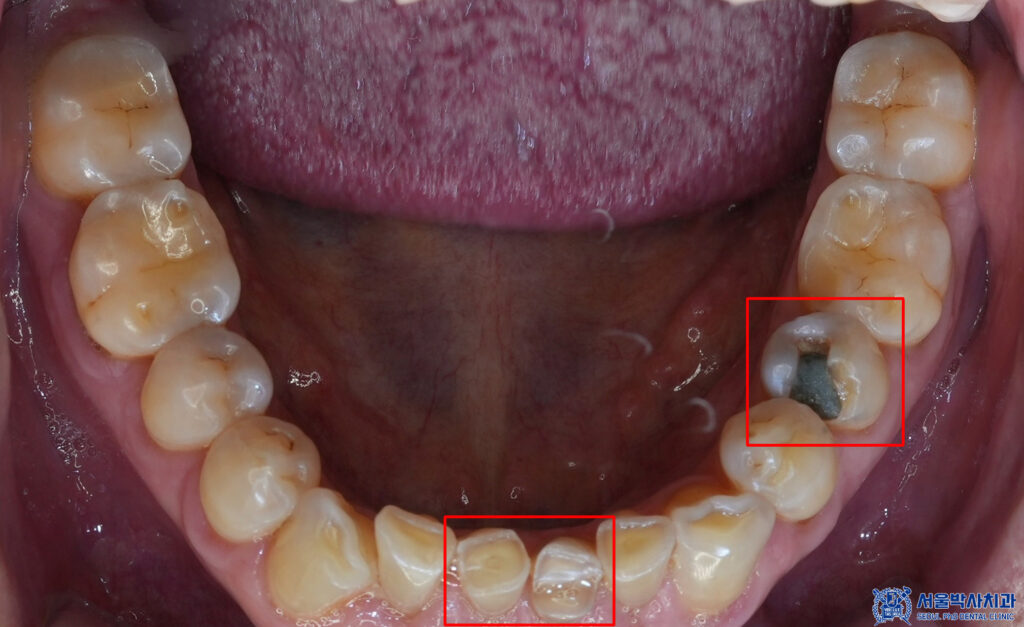

확인해 보니,

아래 앞니의 파절이 있어,

심미적으로 치아가 갈려서

없어진 것처럼 보였습니다.

또한 왼쪽 아래 작은 어금니는

기존 충전재 하방으로

충치가 생겨있는 것을

확인할 수 있었습니다.